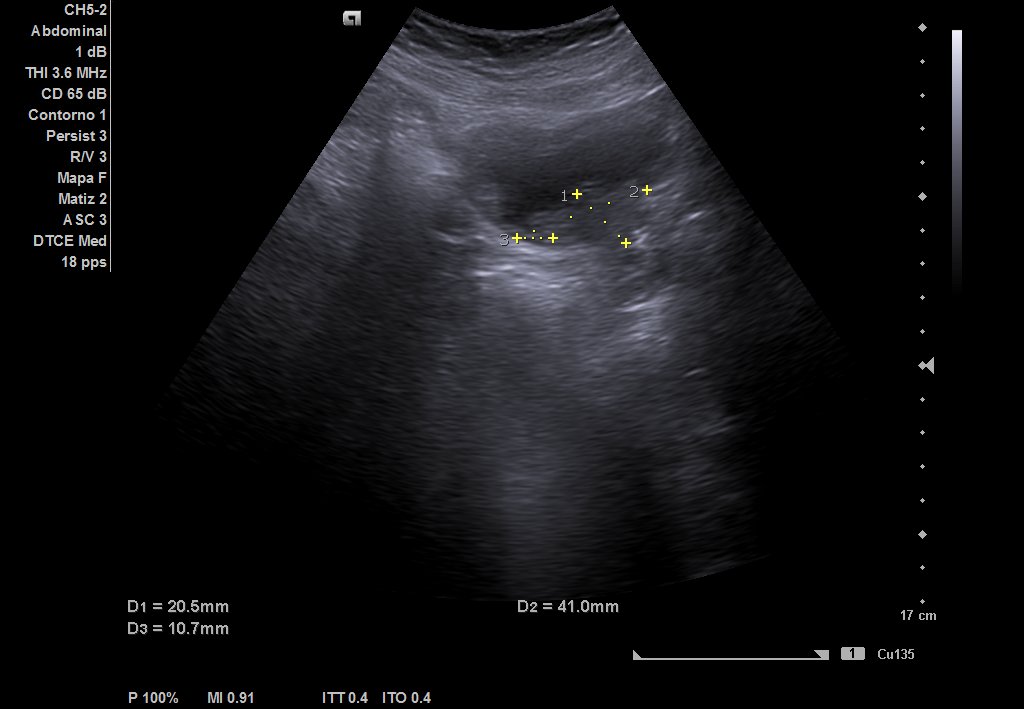

Ecografía urinaria: vejiga bien replecionada, observándose masa en trígono de 20 x 12 mm. Riñón derecho con dilatación pielocalicial moderada, sin hidronefrosis. Riñón izquierdo sin alteraciones reseñables.